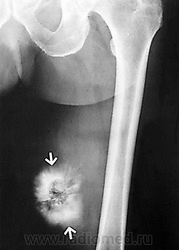

Онкология. Саркома. Экстраскелетная остеосаркома. +

Экстраскелетная остеосаркома мягких тканей - это высокозлокачественная редкая опухоль, составляющая, по данным разных авторов, 1-1,2% всех злокачественных сарком мягких тканей и 4% всех остеогенных сарком, чаще встречается у мужчин и в возрасте 50-60 лет. Ранними клиническими проявлениями являются боль и припухлость, причем чаще отмечается только припухлость. Сроки развития клинических симптомов до начала лечения составляют в среднем от 6 мес до 2 лет. Наиболее часто опухоль поражает нижние конечности - бедро в 47-70% случаев, в 20-23% - верхние конечности, в 7-17% случаев опухоль локализуется ретроперитонеально. Внескелетные остеогенные саркомы могут встречаться в печени, желчном пузыре, молочной железе. Наличие внескелетной остеогенной саркомы позволило предположить о возникновении данной опухоли из мультипотентных мезенхимальных клеток.

Прогноз заболевания остается плохим, чувствительность к химиотерапии очень низкая. Диагноз экстраскелетной остеосаркомы может быть установлен только после исключения наличия костных очагов опухоли.

Снимки из из архива AFIP